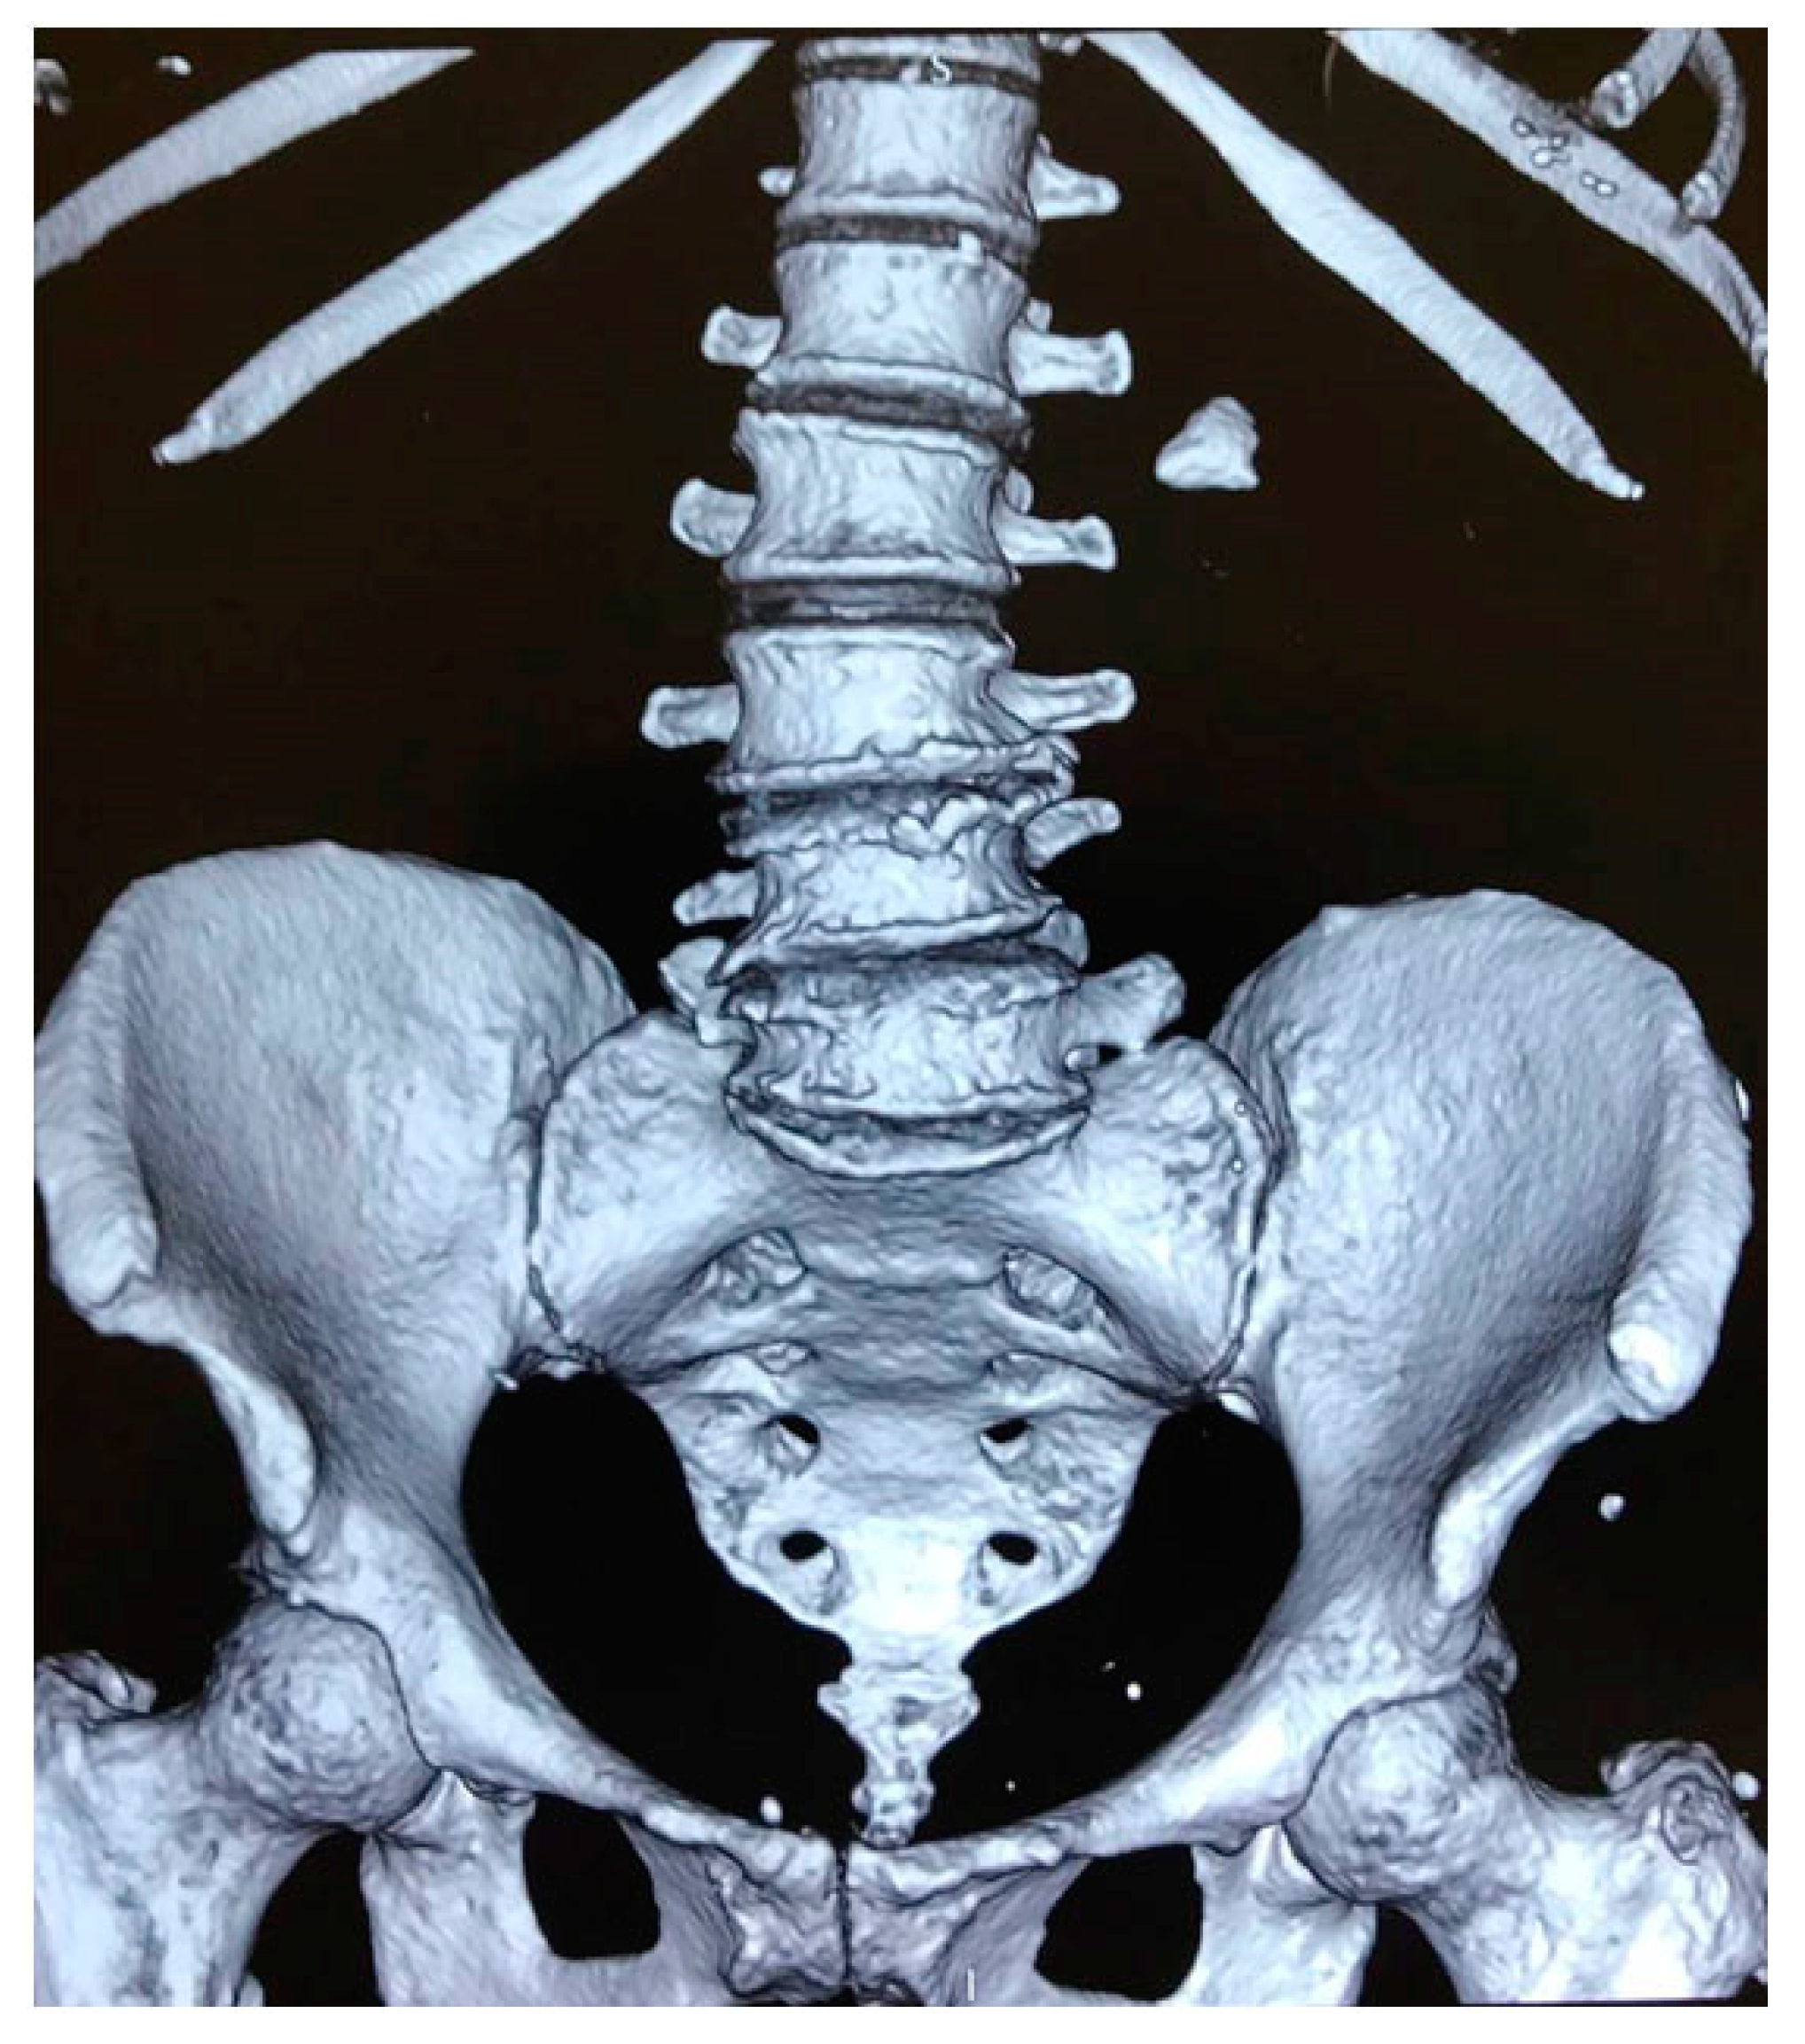

3.2. Clinical Case